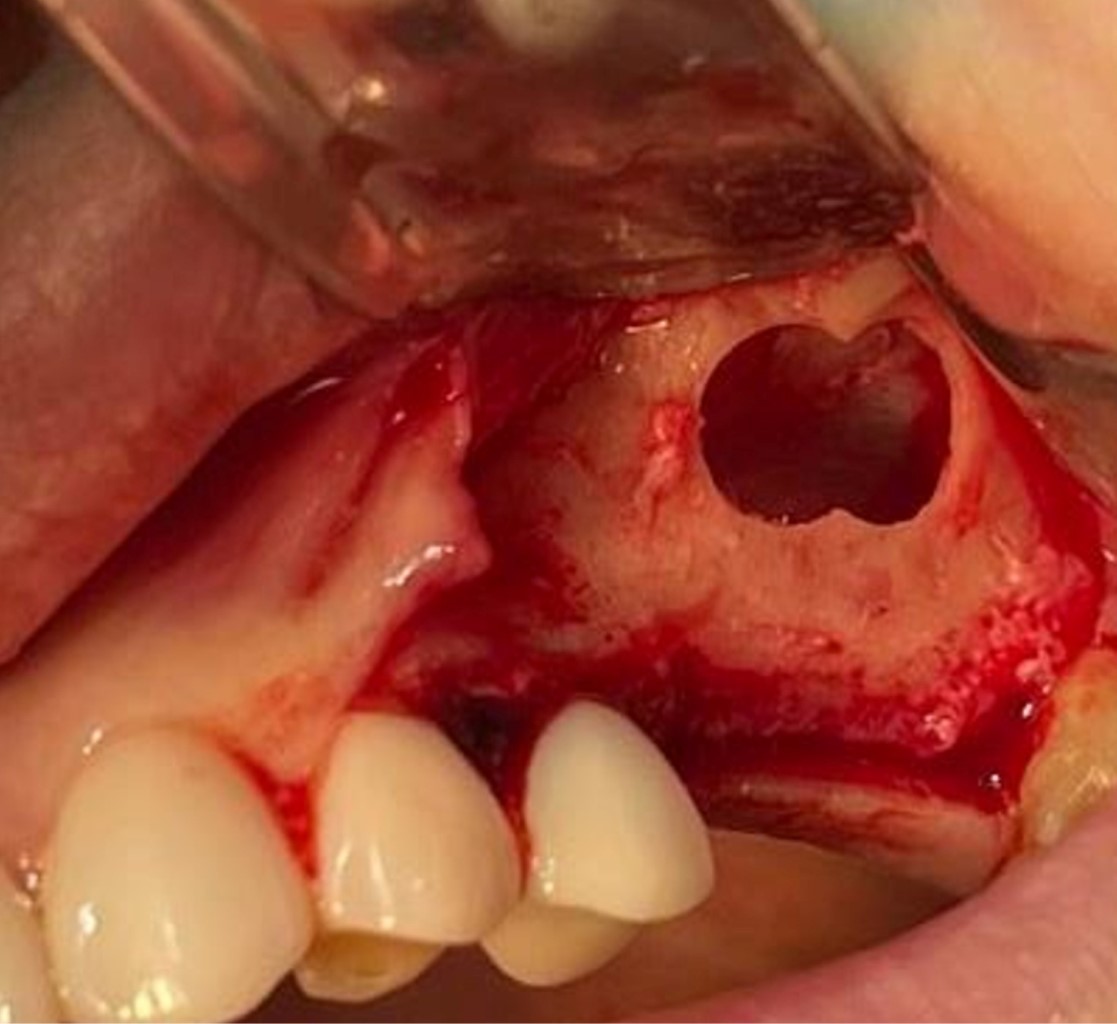

Figure 4